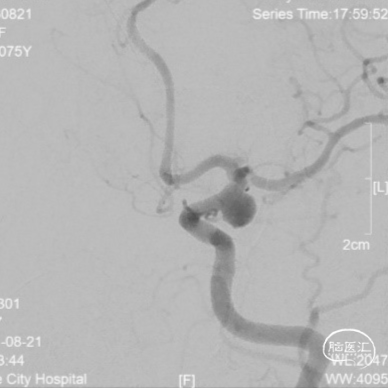

DSA:后交通动脉瘤(瘤体6.7mmx5.6mm,瘤颈5.2mm)合并A1起始部微小动脉瘤(瘤体1.7mmx1.9mm,瘤颈1.7mm)且指向后方。

左侧后交通动脉瘤破裂出血

左侧A1起始部微小动脉瘤